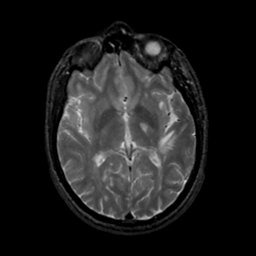

MR Study #18, July 21, 1991 -- Slice #25